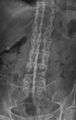

-

X-ray showing bamboo spine in a person with ankylosing spondylitis.

CT scan showing Bamboo spine in ankylosing spondylitis